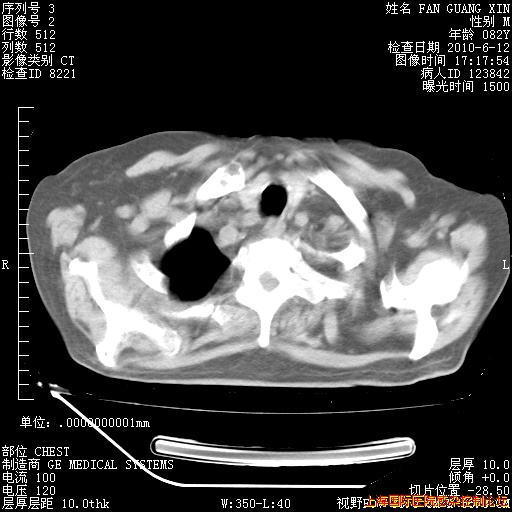

补发6月12日肺部CT肺窗

6月12日肺窗

6月12日纵膈窗